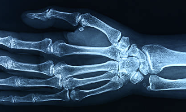

손가락 마디가 붓고 아프면 간단한 일조차 하기가 어렵습니다. 설거지나 청소 같은 일상생활뿐 아니라 업무 중 키보드를 치는 것조차 힘들어져 생활의 질이 크게 저하됩니다. 손가락 마디가 붓고 아픈 증상은 단순히 피로 때문일 수도 있지만, 때로는 심각한 관절 질환의 초기 신호일 수 있어 주의가 필요합니다. 특히 30대 이후 여성은 호르몬 변화나 퇴행성 변화로 인해 더욱 자주 경험합니다. 이번 글에서는 손가락 마디가 붓고 아픈 주요 원인과 증상, 효과적인 대처법을 상세히 정리했습니다.

손가락 마디의 붓기와 통증을 가장 자주 유발하는 원인 중 하나는 퇴행성 관절염(골관절염)입니다. 주로 손을 자주 쓰는 직업을 가진 분이나 중년 여성에게 흔히 나타나며, 관절의 연골이 마모되어 뼈가 서로 부딪히면서 염증과 통증을 유발하는 질환입니다.